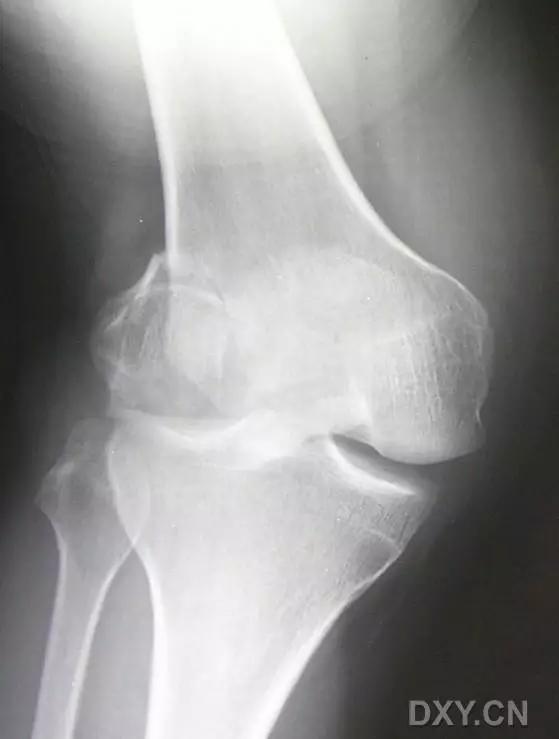

5. Hoffa 骨折

指股骨远端冠状面的骨折。

病例 1:一般股骨髁间、髁上粉碎骨折中含 Hoffa 骨折的不少见,但单纯后髁骨折则很少见。

正位片

侧位片

水平位 CT

第 2 例

第 3 例